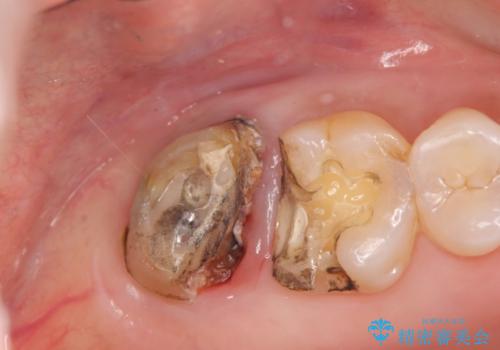

歯髄方向 歯肉方向へと深い 2種類の大きな虫歯

- 他院で虫歯が大きすぎて歯を抜くしかないと言われ、歯を残す手段はないものかと当院へ初診来院されました。

#17は失活歯で歯肉方向への縁下カリエス、#16は生活歯であるものの歯髄ギリギリの処置となるであろうとが予想される治療です。

歯周外科、マイクロスコープを用いた虫歯治療を行い歯を残す治療計画を立てます。